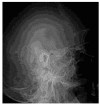

Background: This study presents a comprehensive analysis of cholesteatoma of the middle ear, focusing on its clinical presentation, diagnostic imaging, and treatment outcomes. Cholesteatomas are defined by the keratinized squamous epithelium within the middle ear, leading to significant bone erosion, often affecting the ossicular chain and surrounding structures. Methods: The study explores various mechanisms involved in cholesteatoma progression, including enzymatic lysis, inflammatory responses, and neurotrophic disturbances. The study conducted a retrospective clinical and statistical review of 580 patients over a 20-year period (2003-2023), highlighting the role of advanced imaging, including computed tomography (CT) and diffusion-weighted magnetic resonance imaging (DWI), in preoperative planning and postoperative follow-up. Results: Findings revealed that early detection and intervention are crucial in preventing severe complications such as intracranial infection and hearing loss. Surgical treatment primarily involved tympanoplasty and mastoidectomy, with a recurrence rate of 1.55% within two years. The study underscores the importance of integrating imaging advancements into clinical decision-making to enhance patient outcomes and suggests further investigation into molecular mechanisms underlying cholesteatoma progression and recurrence. Histopathological and microbiological analysis was performed to identify pathological patterns and microbial agents. Conclusions: The study highlights the importance of early diagnosis and intervention to prevent complications such as intracranial infections and permanent hearing loss, while also emphasizing the role of advanced imaging techniques in the management and long-term monitoring of cholesteatoma patients.